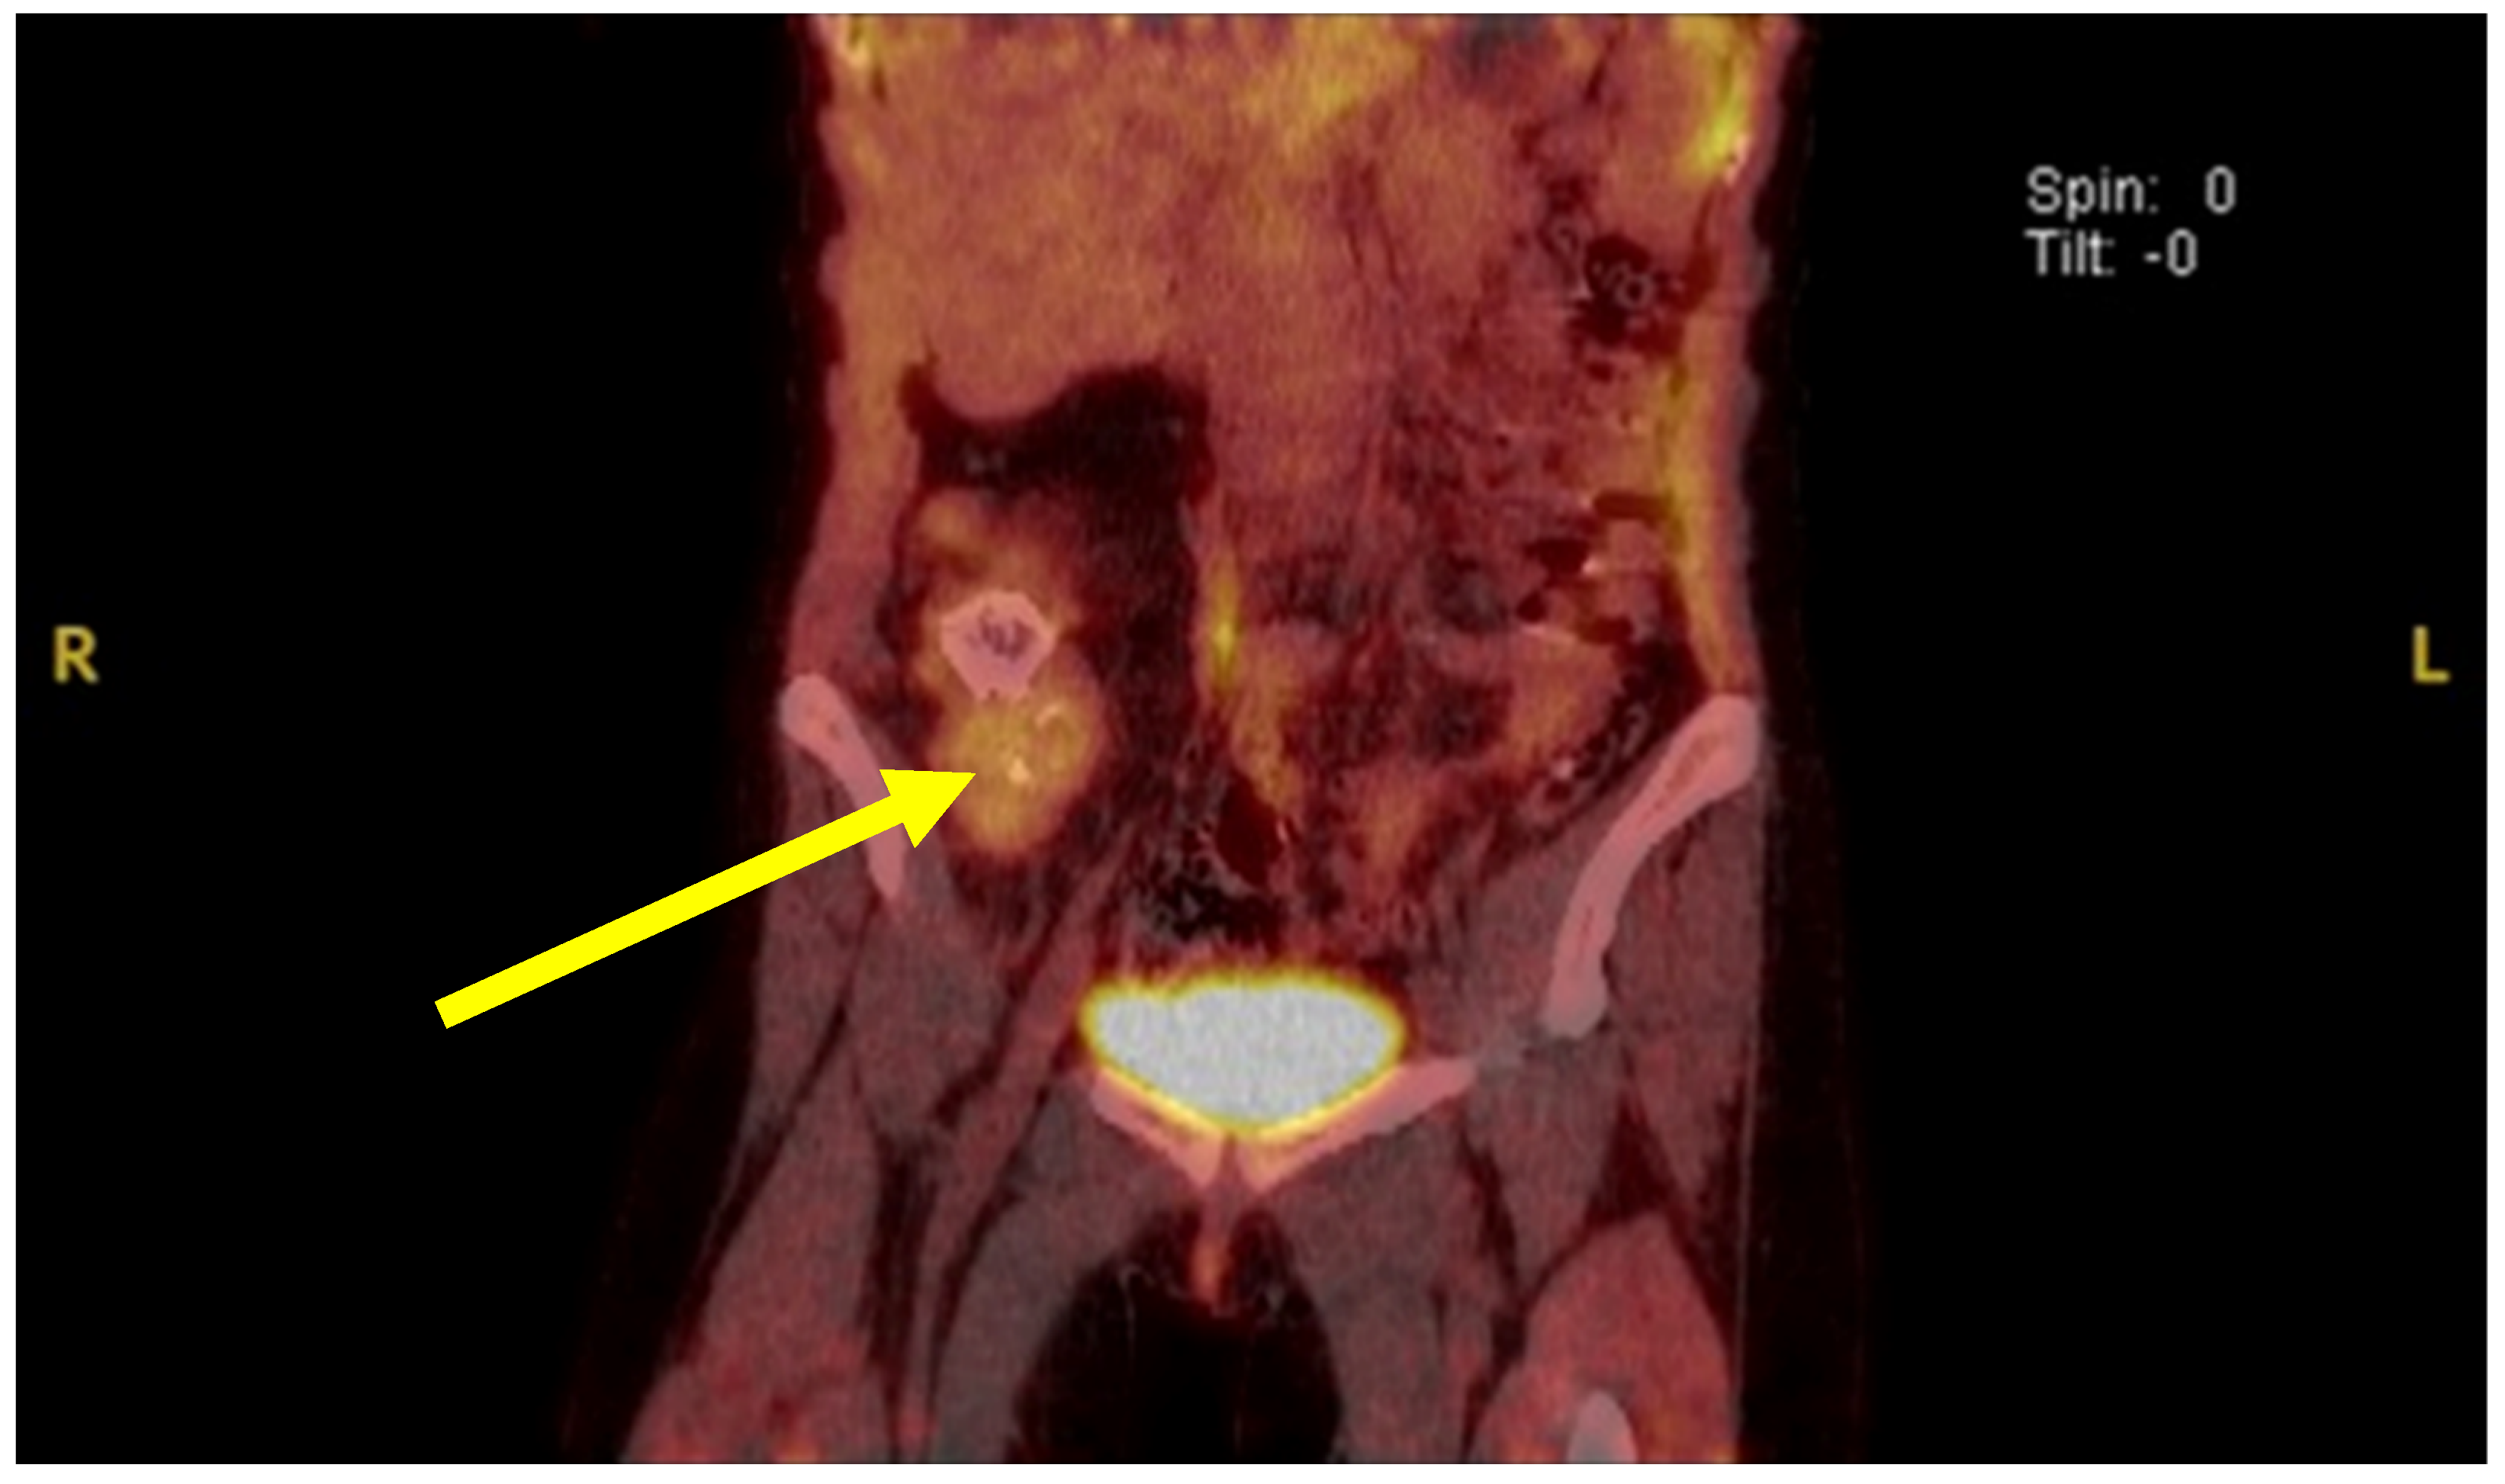

A PET-CT scan showed increased uptake in the right lower quadrant of the abdomen, highly suspicious for an extraluminal mass (Figure 3). During work-up, the patient developed severe respiratory distress, which, despite high-dose steroid administration and supportive therapy, led to endotracheal intubation and to placement on mechanical ventilation. Given the development of severe respiratory failure prior to abdominal surgery and before a donor lung became available, veno-venous extracorporeal membrane oxygenation (VV-ECMO) was initiated as a bridging strategy. This measure provided stabilization and adequate oxygenation, allowing the patient to survive until definitive surgical resection and subsequent transplantation could be carried out. Simultaneously, the patient was evaluated for lung transplantation.

Figure 3.

PET-CT scan of the abdomen showing focal hypermetabolic activity. Coronal fused PET-CT image reveals a localized area of increased fluorodeoxyglucose (FDG) uptake in the right lower quadrant of the abdomen (indicated by the yellow arrow). The hypermetabolic focus is suggestive of an active lymphoproliferative lesion, potentially corresponding to the intra-abdominal mass later confirmed as unicentric Castleman’s disease. Image reproduced from Bender et al. [11], under the terms of the Creative Commons Attribution 4.0 International License.